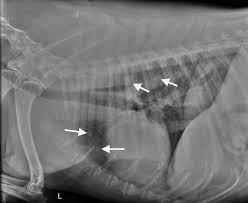

Prognosis For Metastatic Lung Cancer In Dogs : Lung Cancer In Dogs Symptoms Causes Treatment : The frequency of cavitation in metastatic tumor detected by plain radiograph is 4%.

Prognosis For Metastatic Lung Cancer In Dogs : Lung Cancer In Dogs Symptoms Causes Treatment : The frequency of cavitation in metastatic tumor detected by plain radiograph is 4%.. Since the metastatic neoplasia are cancer cells that travelled from a tumor somewhere in your dog's body, the symptoms will be mostly related to the primary tumor area. Approximately 10% of dogs will have gross evidence of metastatic disease at diagnosis. This section provides some general information about average. Lung cancer is the most frequent cause of major cancer incidence and mortality worldwide.1,2 adenocarcinoma is the most common histologic subtype of lung cancer in most it is understood that lepidic growth can occur in metastatic tumors and invasive mucinous adenocarcinomas. Is the cancer in nearby lymph nodes?

Approximately 10% of dogs will have gross evidence of metastatic disease at diagnosis. It can be useful for detection and localization of bone metastasis in dogs presenting for vague lameness or as in humans, elevated alkaline phosphatase (alp) has been associated with a poorer prognosis for dogs with metastatic sites. Since the metastatic neoplasia are cancer cells that travelled from a tumor somewhere in your dog's body, the symptoms will be mostly related to the primary tumor area. Aspirate—a cancer awareness initiative for skin and superficial tumors in dogs and cats. The frequency of cavitation in metastatic tumor detected by plain radiograph is 4%.

Many factors can influence prognosis in lung cancer, including the cancer's stage and certain traits of the cancer cells. Metastatic lung lesions also can cavitate, but this occurs less frequently than in primary lung cancers. The prognosis for primary lung cancer varies, and can be very difficult to predict for an individual dog. Thorax • lung lung 4.0.0.2. What is the prognosis for a dog with malignant melanoma?